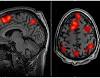

PET scans reveal early signs of Parkinson's and Lewy body disorders The abnormal accumulation of α-synuclein protein is a defining pathological feature of several neurodegenerative conditions collectively known as synucleinopathies, including Parkinson's disease (PD), multiple system atrophy (MSA), and dementia with Lewy ...